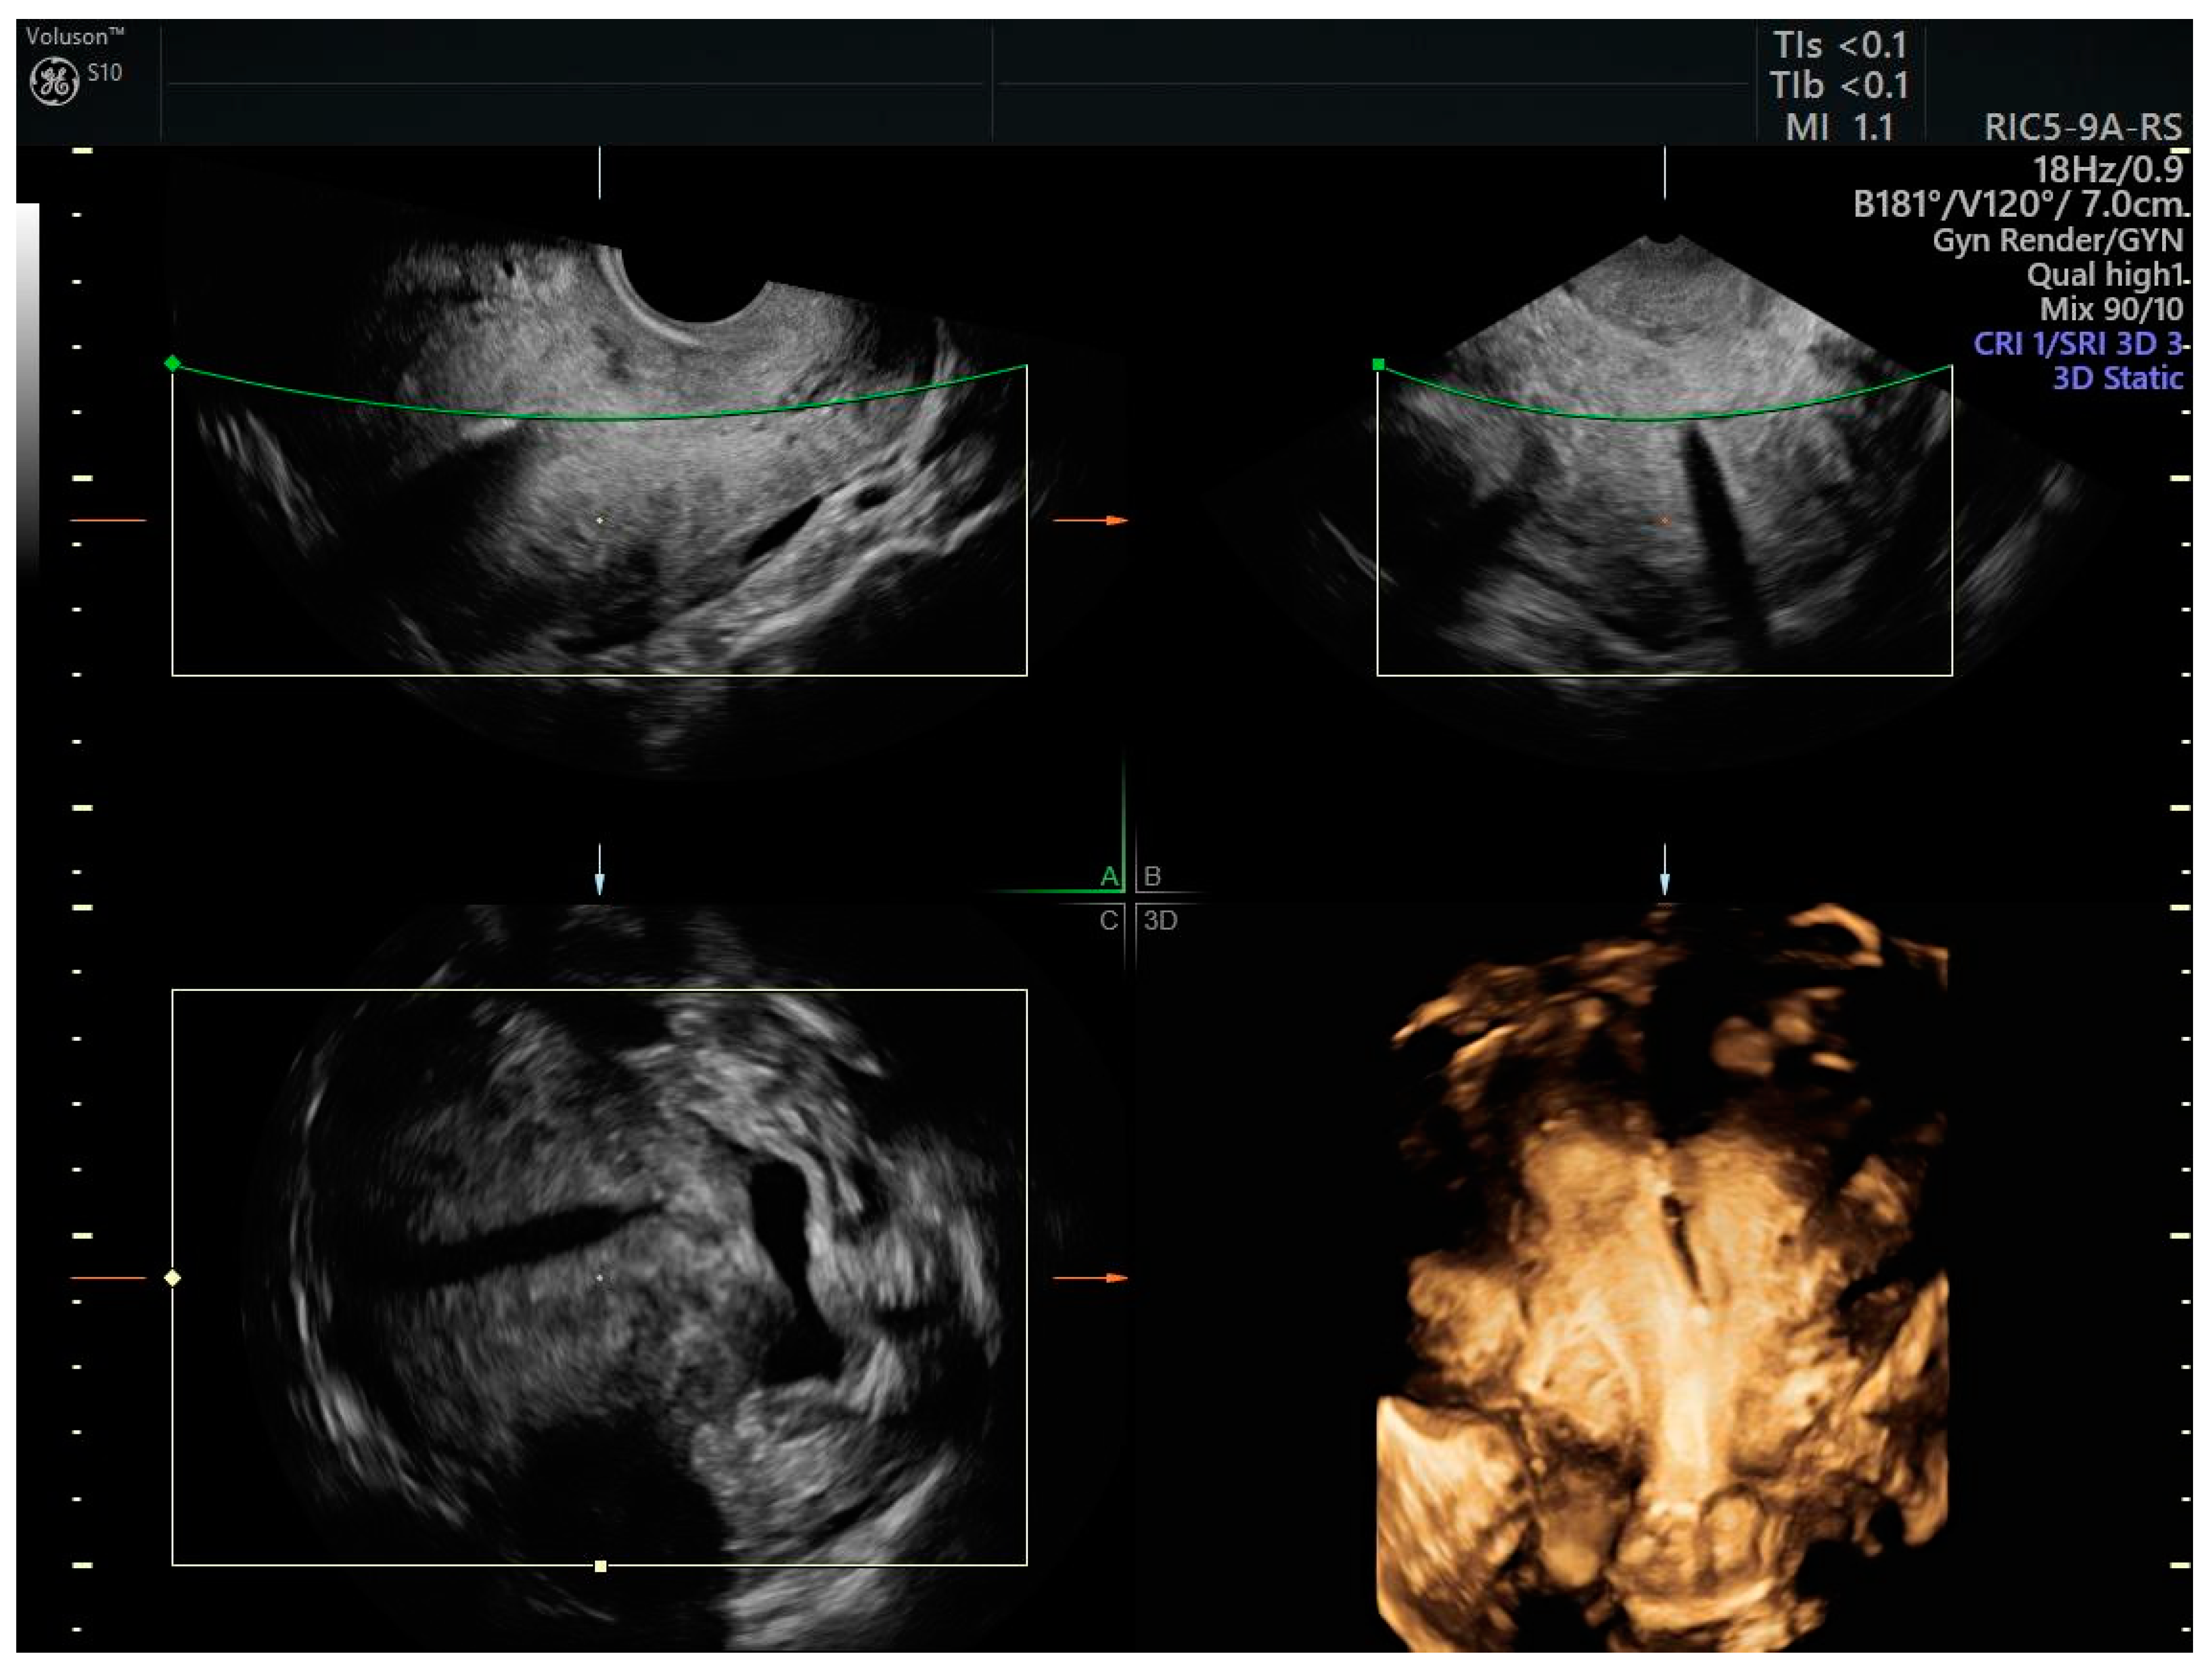

- No evidence of myometrial infiltration;

- No evidence of extrauterine pathology on imaging (TVS/RM/CT);